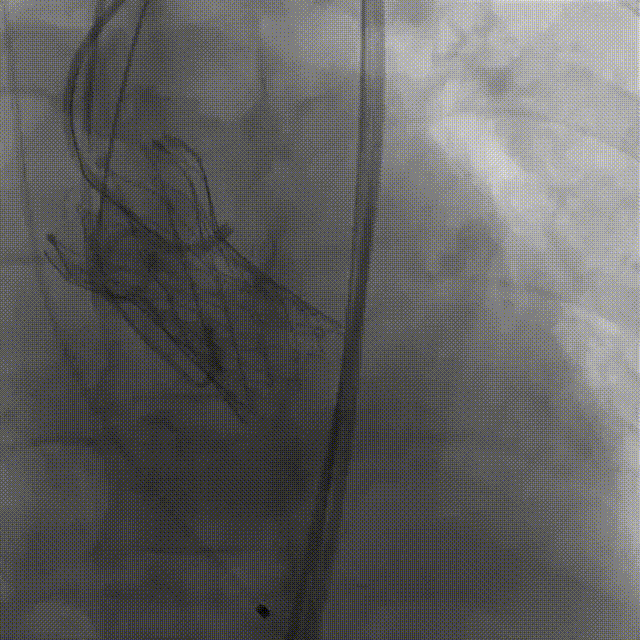

5.右冠行支架保护

6.右冠造影

7.输送器过弓

8.瓣膜定位